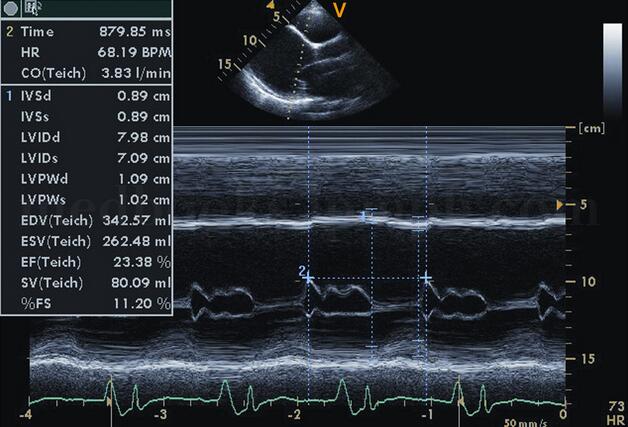

(4)左心室收缩功能减低:左室射血分数(EF)≤30%,左室短轴缩短率(ΔD)≤15%~20%(见图2‐1‐188)。

图2‐1‐188 左室收缩功能减低,EF、ΔD减低